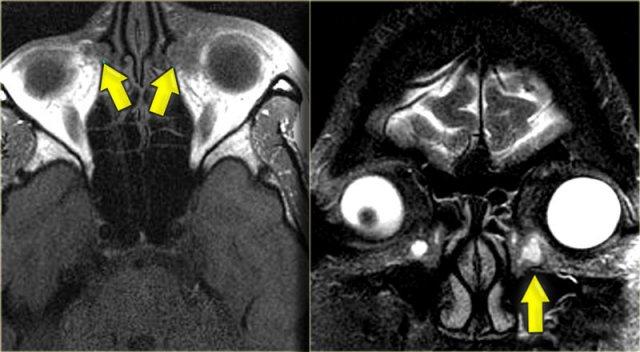

Bên trái là chuỗi xung T1W mặt phẳng axial, bên phải là chuỗi xung T2W mặt phẳng coronal.

Có bất thường ở bên trái, nhưng ở mức độ ít hơn cũng có ở bên phải.

Hãy cố gắng xác định các cấu trúc nào bị tổn thương.

Các mũi tên vàng chỉ vào ống lệ mũi.

Túi lệ kết nối với ống lệ, sau đó dẫn lưu vào ngách mũi dưới.

Bên trái có phù nề mô mềm quanh hốc mắt trước vách ngăn.

Trên hình ảnh coronal, có tín hiệu cao hai bên tại vị trí nối giữa ống lệ mũi và túi lệ, gợi ý ổ dịch.

Bên trái cũng có phù nề mô xung quanh.

Chuỗi xung T1W sau tiêm thuốc tương phản từ, mặt phẳng axial và coronal.

Ở phía ngoài ống lệ mũi hai bên, có các ổ dịch hiện nay cho thấy hình ảnh ngấm thuốc ngoại vi.

Các hình ảnh bổ sung (chuỗi xung T2W) cho thấy bệnh lý niêm mạc xoang hàm phải và mức dịch trong xoang hàm trái, ngoài ra còn có bệnh lý xoang sàng và xoang bướm lan rộng.

Bệnh nhân này bị viêm xoang cấp tính có biến chứng viêm mô tế bào hốc mắt và viêm túi lệ kèm áp xe.

Hẹp ống lệ mũi do bẩm sinh hoặc do viêm là yếu tố nguy cơ dẫn đến viêm túi lệ.